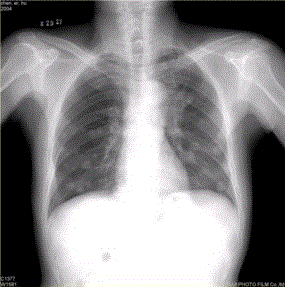

问题 患者男,45岁,因肝硬化、肝癌行肝移植术后6个月,咳嗽2周,来院复查。CR及CT影像如下图。 肺内转移结节可为

选项 A.弥漫性粟粒结节 B.单发结节 C.结节发生坏死形成空洞 D.钙化结节 E.带毛刺的结节 F.含脂肪成分的结节

答案 ABCDE

解析 ABCDE